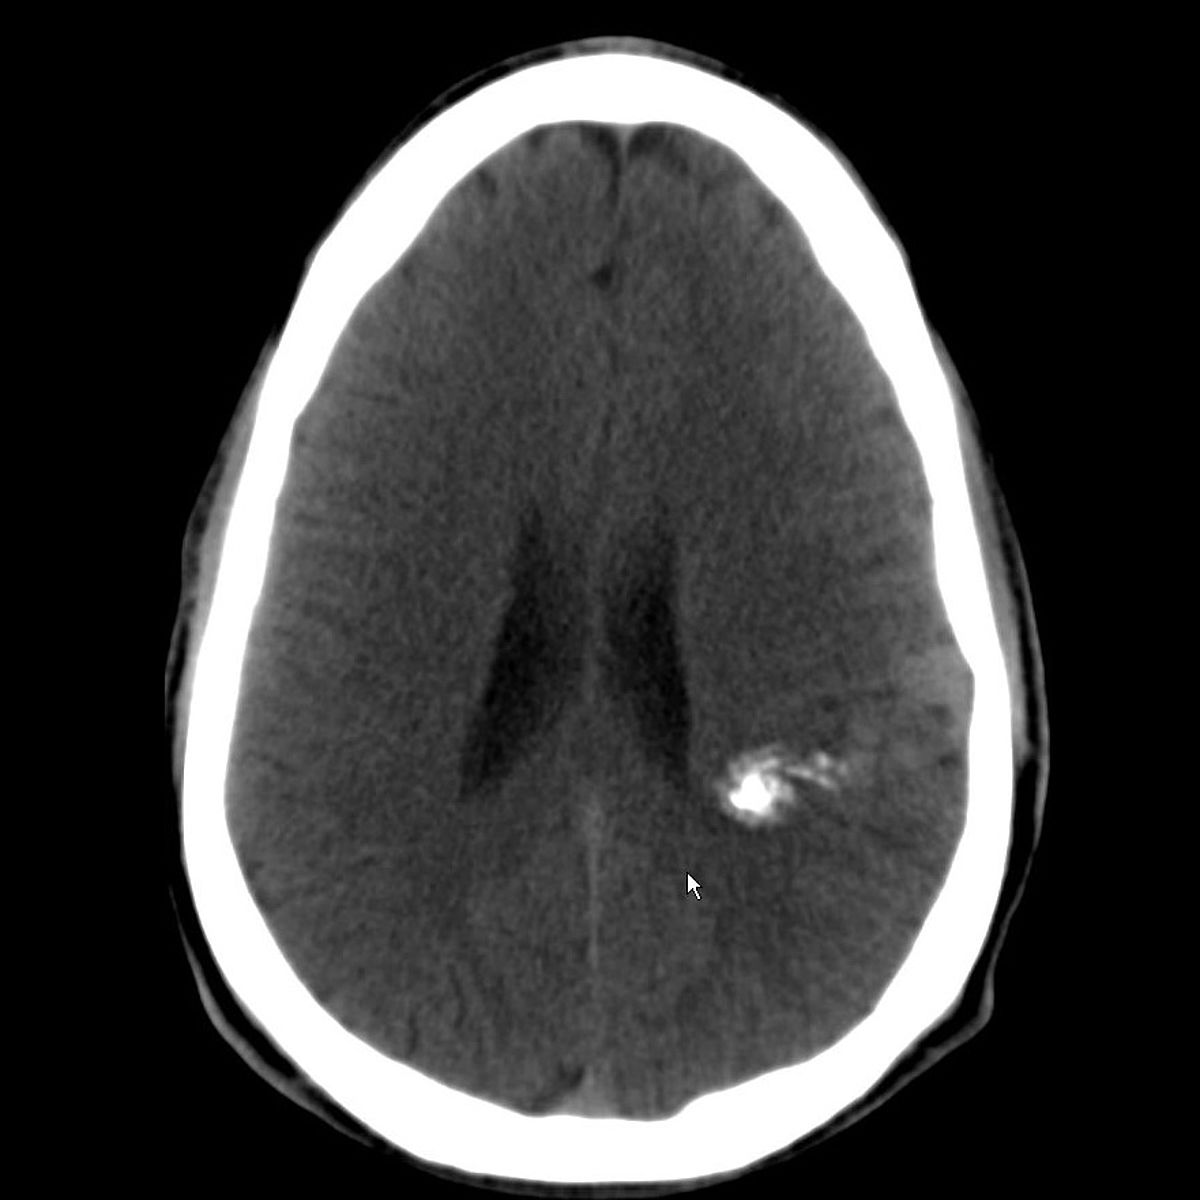

Gefäßmissbildungen und -tumore können zu Blutungen führen, aufgrund ihrer Größe lokale Probleme verursachen oder auch nur rein ästhetisch störend sein.

Die Neuroradiologie ist bei der Diagnostik solcher Gefäßveränderungen mit Computertomographie, Kernspintomographie und vor allem der Angiographie gefragt.

Im Rahmen der interventionellen Therapie sind endovaskuläre und perkutane Injektionen mit verödenden Substanzen, Gewebe- und Gefäßkleber möglich.